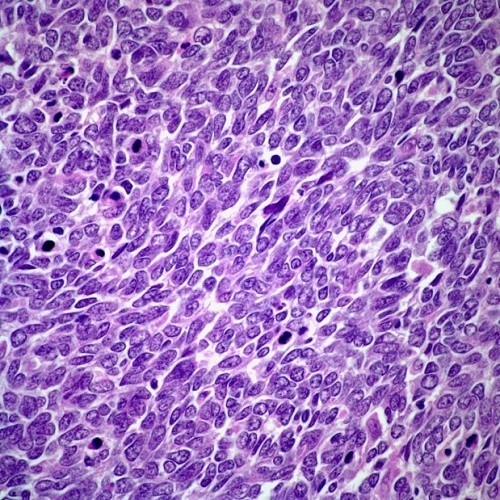

Ung thư phổi chia thành 2 loại: ung thư phổi không tế bào nhỏ và ung thư phổi tế bào nhỏ. Trong đó, ung thư phổi tế bào nhỏ chiếm 15% – 16% các trường hợp ung thư phổi và là loại ung thư phổi nguy hiểm nhất. Đây là loại ung thư phổi phát triển nhanh chóng, nó có thể di căn tới rất nhiều bộ phận khác trên cơ thể nên rất khó có thể loại bỏ triệt để các khối u bằng phương pháp phẫu thuật. Tuy nhiên, ung thư phổi tế bào nhỏ thường đáp ứng tốt với hóa trị liệu ban đầu. Tuy nhiên, nó có xu hướng tái phát sau điều trị ban đầu và có khả năng kháng điều trị nhiều hơn trong lần hóa trị liệu tiếp theo.

Ung thư phổi tế bào nhỏ chiếm 15% – 16% các trường hợp ung thư phổi